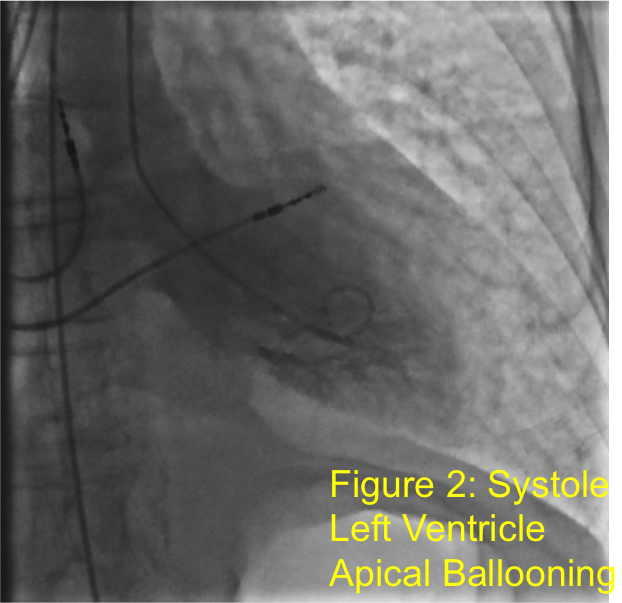

Case Presentation: Patient is a 71 year old female with hypertension and chronic obstructive pulmonary disease who presented after syncopal episodes and falls. She denied chest pain but did have lightheadedness and shortness of breath (SOB). She was started on transcutaneous pacing by EMS due to severe bradycardia. Admission EKG (fig 1) showed 3rd degree atrioventricular (AV) block and NSTEMI with troponin of 0.97 ng/mL. She was treated with Atropine and Cardiology implanted a pacemaker. First transthoracic echocardiogram (TTE) showed normal left ventricular function, but a few days later, she developed acute SOB due to pulmonary edema and heart failure. Second TTE showed hypokinesis and decreased ejection fraction from 55% to 20% (LVEF). Cardiac catherization showed diffuse small coronary vessels but no discrete culprit lesions and left ventricle apical ballooning (fig 2). She was diagnosed with Takotsubo Cardiomyopathy (TC) and further treatment included mechanical ventilation, hemodialysis, Milrinone drip and intra-aortic balloon pump. Subsequent TTE showed improvement in LVEF to 45%. She was discharged on Propranolol and Lisinopril but she returned promptly for respiratory distress requiring one more day of mechanical ventilation. CT chest showed bilateral pleural effusions requiring diuresis. Interestingly, on admission, thyroid stimulating hormone (TSH) was noted to be 0.256 mIU/L (0.34-5.60) with free T4 of 1.53 ng/dL (0.70-1.50). On re-admission, her TSH was 0.054 mIU/L and free T4 was 2.45 ng/dL. Thyroid Stimulating Immunoglobulin (TSI) level was < 0.10 IU/L (0.00-0.55). Thyroid Ultrasound was negative for nodules and she was started on Methimazole for thyrotoxicosis.